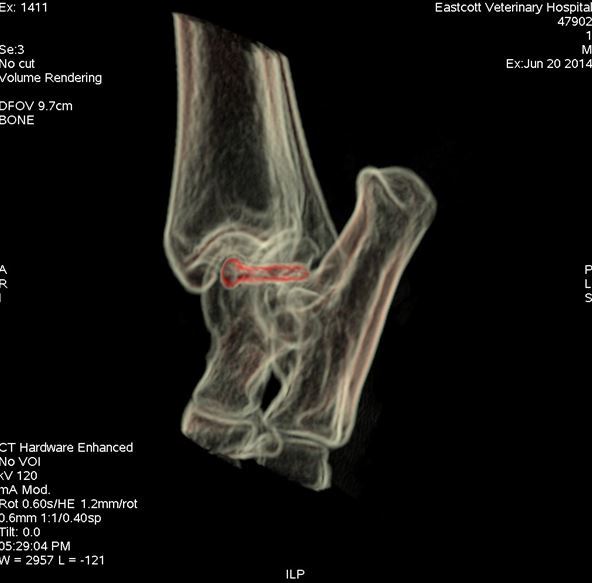

Post-operative CT scan showing position of screw (red) stabilising medial talar ridge fracture

Figure 4